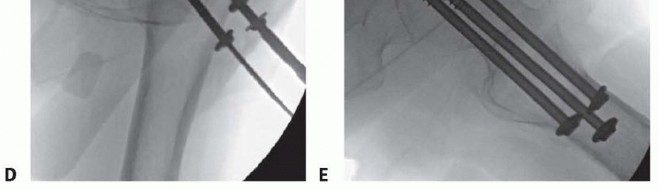

Cephalomedullary Nail Fixation The patient is positioned on the fracture table as noted earlier, fluoroscopic visualization is confirmed, and the leg and hip is prepared and draped in a sterile fashion. Circumferential proximal thigh preparation is important. Preoperative antibiotics are given.

### Incision and Dissection

A small incision, usually 3 to 4 cm long, is made several centimeters proximal to the tip of the greater trochanter to allow passage of the nail ( TECH FIG 4). A periosteal elevator can be used to spread the gluteus medius fibers in line with the incision. Blunt dissection with an elevator or a finger provides access to the starting point. The tip of the greater trochanter is palpated. The tendon of the gluteus medius attaching to the trochanter can be felt and is protected.

### Starting Point and Reaming

Using fluoroscopy, a starting point is obtained for the nail at the medial edge of the greater trochanter for a trochanteric-starting cephalomedullary nail. The starting point should be just lateral to the piriformis fossa ( TECH FIG 5A). Alternatively, an awl can also be used to obtain the proper starting point; this can be especially useful in obese patients. An anatomic reduction of the femoral neck must be achieved before reaming. If an anatomic reduction cannot be achieved by closed means, an open reduction must be performed.

---

TECH FIG 4 • Landmarks for cephalomedullary nail placement. The iliac crest is marked and the trochanter is outlined. The incision is in line with the femoral shaft and several centimeters proximal to the tip of the trochanter. This can be done by a Smith-Petersen or Watson-Jones approach, as described earlier. An antirotational pin may be used to maintain reduction ( TECH FIG 5B,C). Once reduction has been obtained, the entry reamer is introduced ( TECH FIG 5D). For a short cephalomedullary nail, the entry reamer is all that is needed before nail passage. If a long cephalomedullary nail is being placed, serial reaming can be performed to 1 to 1.5 cm over the desired nail diameter. ### Proximal and Distal Interlocking After the nail is positioned at the correct depth, the guidewire into the femoral head is placed. Multiple fluoroscopic images are needed to make sure the tip of the guidewire is placed within the center of the femoral head for nails with a single screw going into the head. Newer nails with more than one screw going into the head may necessitate adjustments to this technique to allow passage of both screws (such as placing the first lag screw slightly superior to center to allow passage of the second screw inferior to center). A depth gauge is used to check the length of the guidewire. For rotationally unstable femoral neck fractures, an antirotational guidewire or screw can be placed to prevent rotation of the fracture with tapping ( TECH FIG 6A). Many nail systems allow a pin to be placed through a sheath attached to the jig or have an antirotational bar. A reamer is then used to open the outer cortex of the femur and is continued into the head under fluoroscopic guidance. The reamer should be checked during passage to ensure the guidewire is not being driven into the pelvis and the reduction is not lost during reaming. The lag screw is then tapped, and fluoroscopy is again used to ensure the reduction is not lost. The lag screw is placed and fluoroscopy undertaken in multiple views to rule out penetration of the subchondral surface. If a distal interlock is desired, it is then placed. Most nail systems have a set screw that needs to be advanced to give rotational control to the lag screw. If compression is desired, the set screw then needs to be loosened, usually a quarter-turn of the screwdriver, according to the recommendations of the individual nail system being used. As mentioned earlier, appropriate films should be taken with the patient aslee This may include plain films if fluoroscopy is not adequate ( TECH FIG 6B,C). 383

### TECH FIG 5 • A. Intraoperative AP fluoroscopic view showing starting point at medial edge of greater trochanter, in line with the mid-axis of the intramedullary canal. B. Intraoperative photograph showing longer incision distally used to obtain anatomic reduction with temporary stabilization pin placed to maintain reduction. C. Intraoperative lateral fluoroscopic view showing position of the temporary stabilization pin and the guidewire. D. Intraoperative AP fluoroscopic view showing the entry reamer with antirotational pin maintaining reduction of fracture.